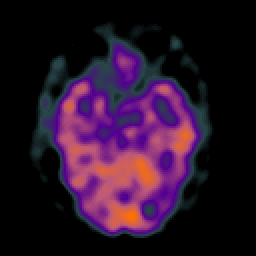

Glioma overlay -- Slice #10

[Home][Help][Clinical] Slice 10